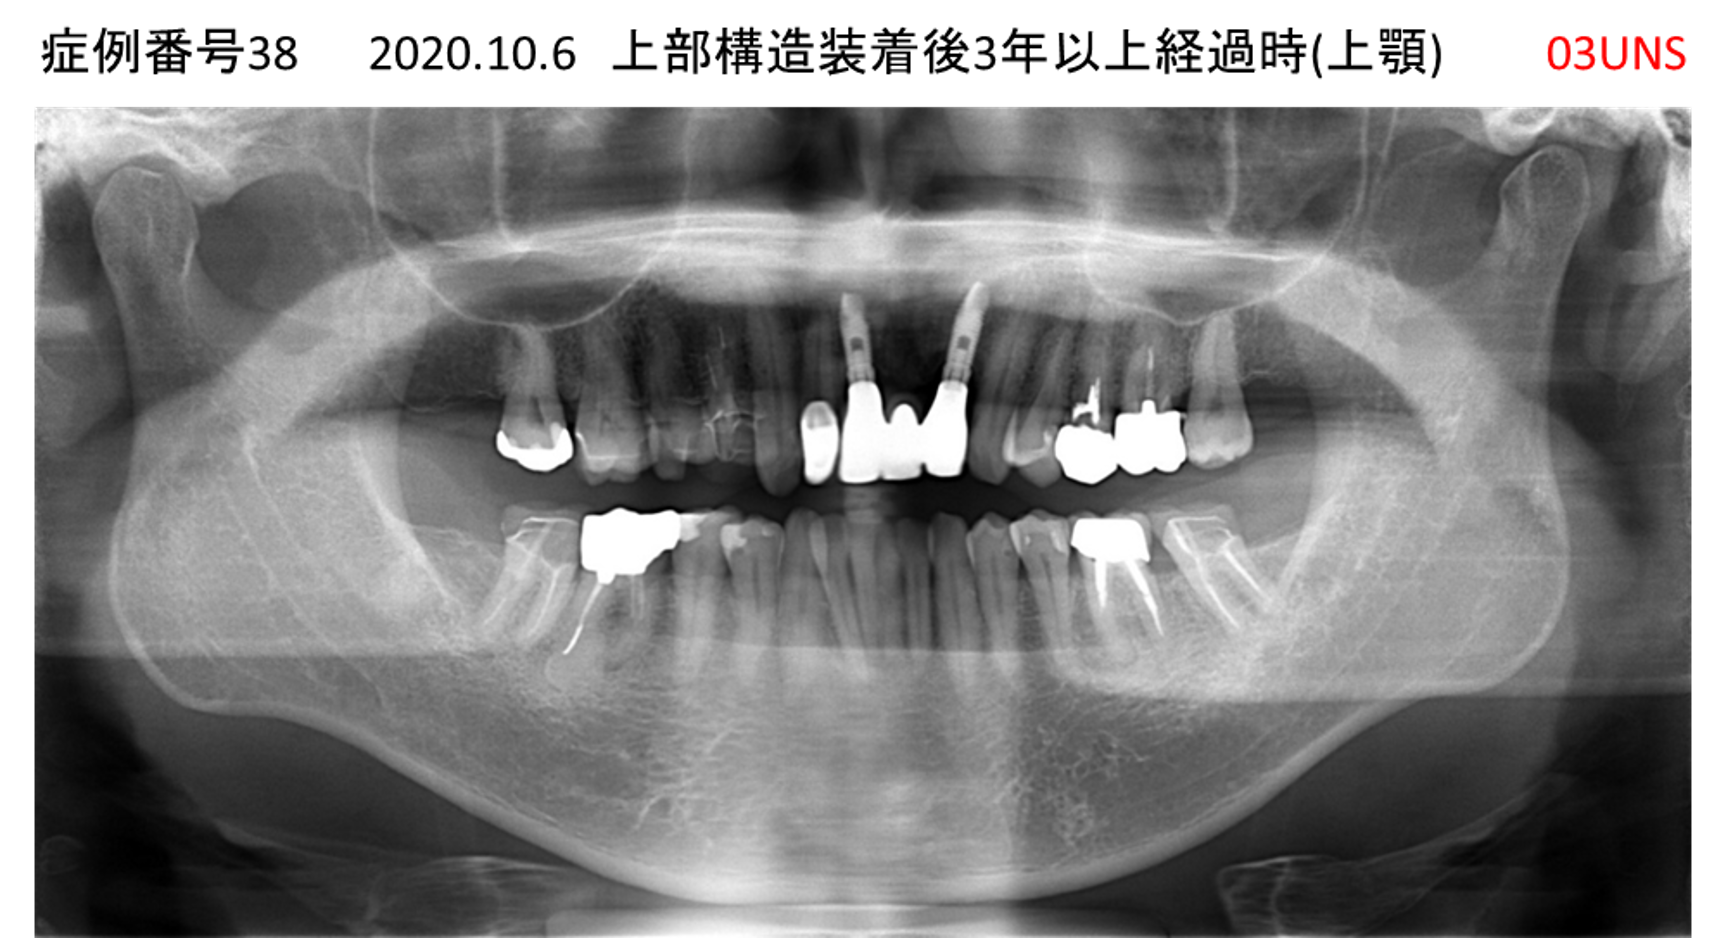

ご飯を美味しく食べたい/人前で笑えるようになりたい患者様のインプラント症例

| 治療名称 |

インプラント |

| 治療費用 |

480万円+税 |

| 治療期間 |

6か月 |

| 患者さんの症状(主訴) |

おいしいご飯が食べられるようになりたい 人前で笑えるようになりたい |

| 治療内容 |

サイナスリフト 抜歯即時インプラント |

| 治療結果 |

何でも食べられるようになった 人前で大口を開けて笑えるようになった |

| 治療の注意点(リスク/副作用) |

インプラントが壊れた場合は再治療が必要 |